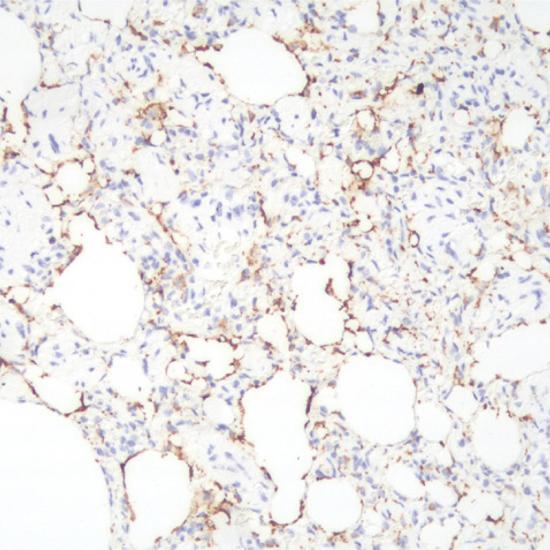

Surfactant Protein B抗體試劑(免疫組織化學(xué)) 閩廈械備20180280號(hào)

• 陽(yáng)性部位:

細(xì)胞漿

• 陽(yáng)性對(duì)照:

肺腺癌

Surfactant Protein B (SP-B)是肺表面活性復(fù)合物的抗原決定簇之一,表達(dá)于肺II型肺泡上皮細(xì)胞, 主要用于肺癌的輔助診斷以及與肺轉(zhuǎn)移癌的鑒別診斷。